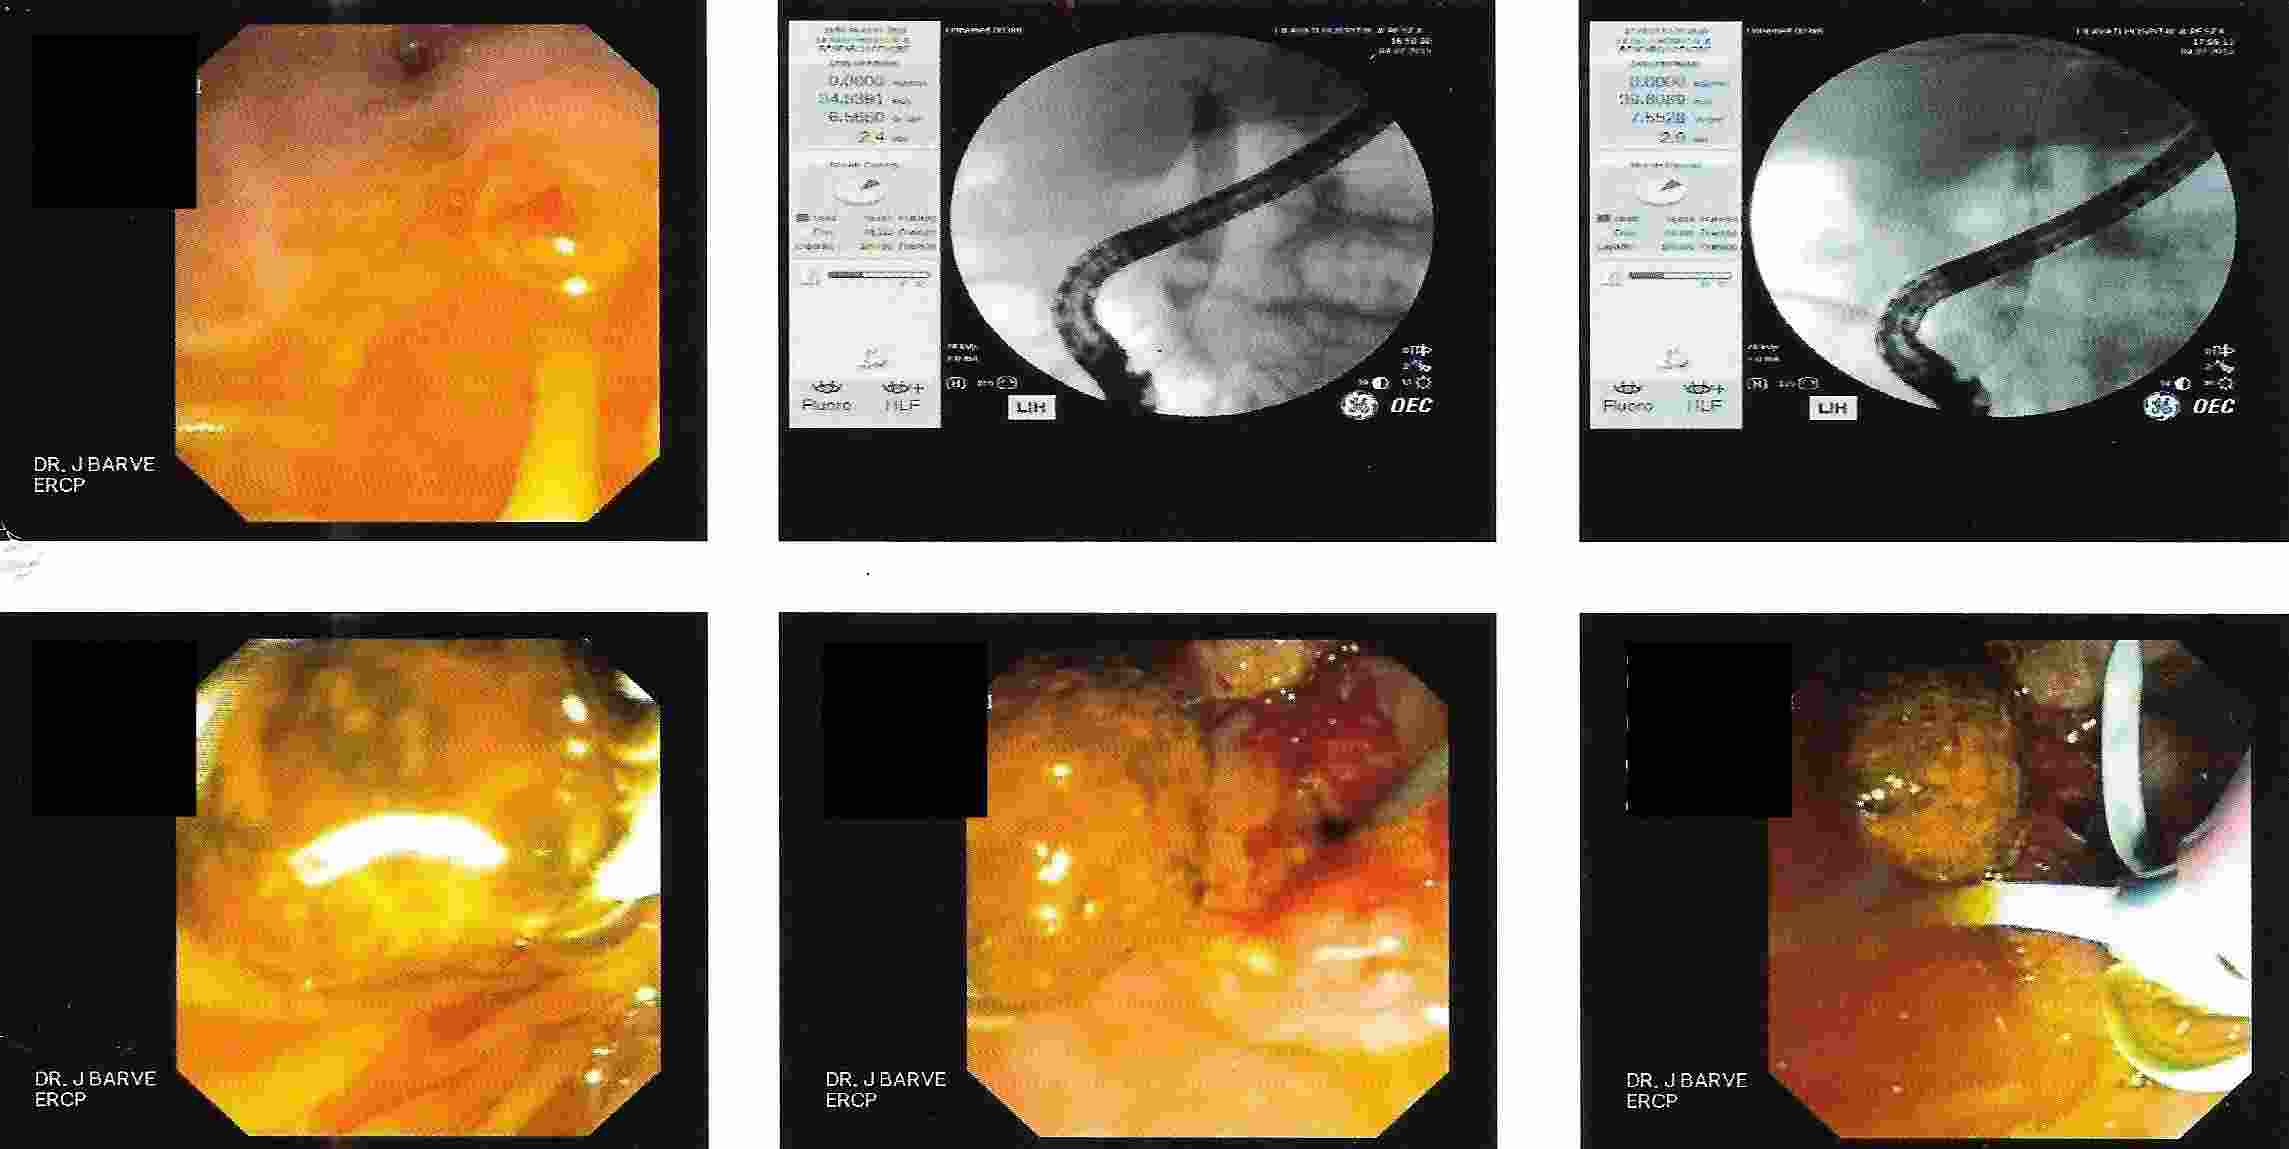

GALL BLADDER STONES TREATMENT

Endoscopic Retrograde Cholangio Pancreatography is an advanced endoscopic procedure related to

diseases of pancreas and biliary tree. Common indication for ERCP is jaundice due to obstruction

of biliary tube, which drains the bile from the liver into the intestine.

Obstruction can be due to a gallstone, which has slipped into bile tube and has blocked the bile tube.

These Stones can be removed by ERCP, without any surgery being involved.

Common Biles Duct Stones

Common Biles Duct Stones

Impacted Stone in Common Bile Duct